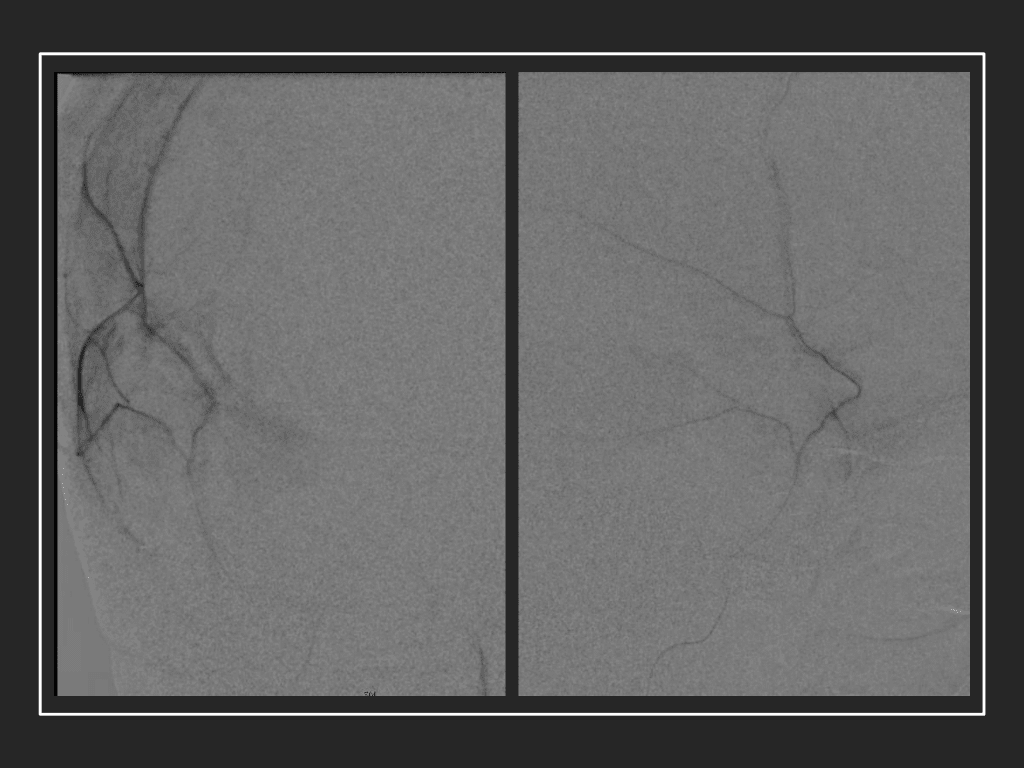

The patient agreed to receive minimally invasive treatment with Bilateral Middle Meningeal Artery Embolization, a new approach to promote resorption of chronic and subacute subdural hematomas in patients that are not improving with conservative measures or have contra-indications to surgical evacuation. Selective catheterization of the Middle Meningeal Artery is followed by transarterial embolization of the territory and inflammatory membranes that are felt to be secreting serosanguinous proteinaceous exceeding the capacity for resorption. MMA embolization was performed bilaterally in this patient. (Figure 2. A and B)

Figure 2. A) Initial right ECA angiogram ; B) Post MMA Embolization; C) Selective Embolization Of Middle Meningeal Artery Membranes using PVA particles (arrows).

Although conventional surgical methods, such as burr hole irrigation or observation in asymptomatic or minimally symptomatic patients have been the mainstay of treatment, middle meningeal artery (MMA) embolization has emerged as a promising adjunctive or alternative treatment. MMA embolization is a neuroendovascular technique which involves placing a microcatheter into the Middle Meningeal Artery, most commonly on the side of the cSDH (occasionally, bilateral embolization has been recommended for larger or bilateral collection. Embolization of both the anterior (frontal) and posterior (parietal) division is performed using a variety of embolic materials (liquid NBCA, Onyx, coils), although polyvinyl alcohol particles of <250 microns are most commonly used to achieve distal penetration and occlusion of the pre-capillary and capillary beds. The micro-leakage of blood and transudative proteinaceous inflammatory fluid in these inflammatory membranes is creating an imbalance in cycle of resorption and preventing resolution or promoting recurrence or growth of these cSDH collections and associated mass effect and midline shift.

Care must be taken to place the microcatheter within a safe position for embolization, with special attention to potential collateral branches to the orbit/eye via sphenoid or meningo-lacrimal branches (which may cause vision loss) or petrosal branches supplying the geniculate ganglion, the tympanic portion of the facial nerve, and often the trigeminal nerve via a branch coursing along the greater petrosal nerve. Once a safe position in the main trunk of the MMA, or superselectively in each of its divisions is achieved, embolization is performed until stasis of contrast and dense contrast staining of the dura is observed within the embolized vascular beds.7

Figure 8. Dense contrast staining of vascular membranes during embolization.